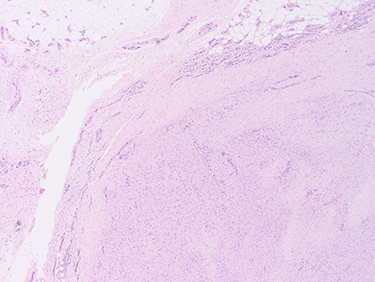

With a radiological diagnosis of LD, the management options were discussed with the patient and her family, who agreed to proceed with surgical excision. A wide local excision was performed; the tissue sent for histopathological analysis, which confirmed the diagnosis of LD (Figs 2 and 3).

Images at ×4 magnification. Tissue samples comprise of cytologically bland spindle cell proliferative features which extends into the adjacent fibrofatty tissue.

The cellular pattern is haphazard with areas of dense fibrosis, suggestive of fibromatosis (LD).